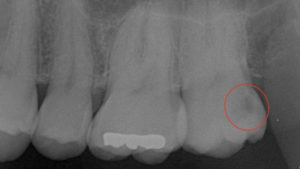

赤丸の範囲に虫歯があります。 ※クリックすると拡大 |

過去に樹脂を詰めたとのことですが、 その下で大きな虫歯になっていました。 |